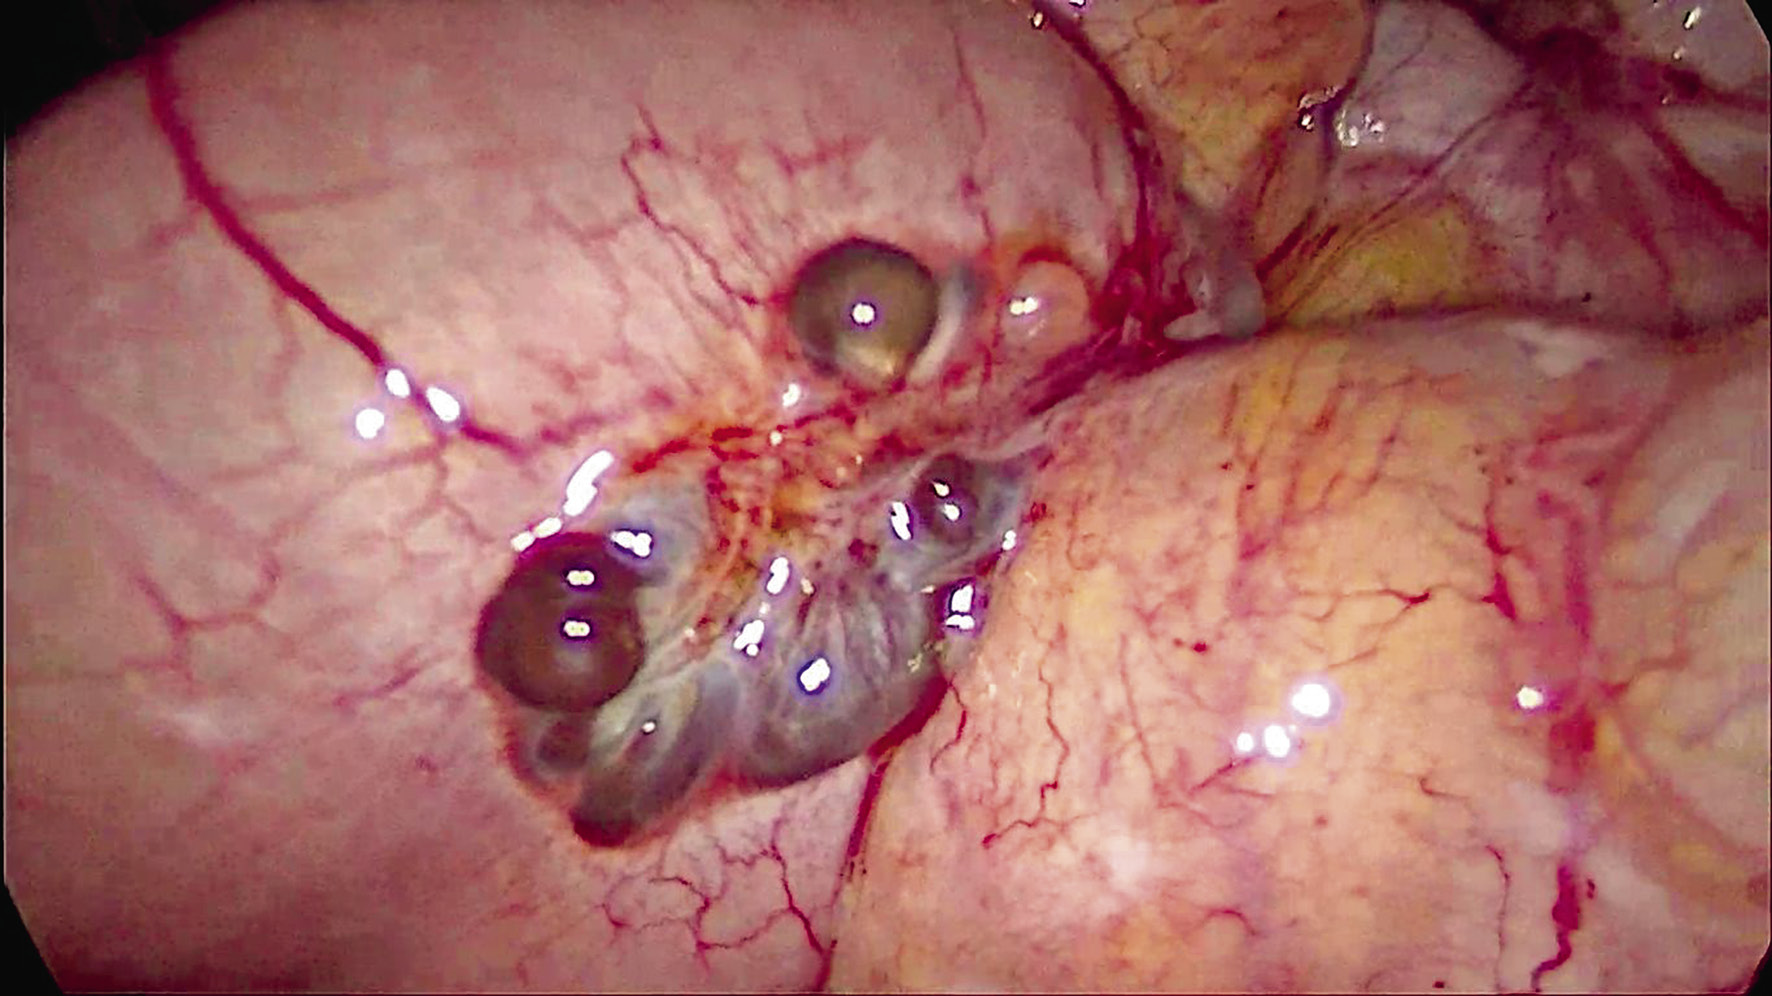

Больной выполнена лапароскопически ассистированная правосторонняя гемиколэктомия. Под эндотрахеальным наркозом выше пупка открытым доступом по Hassen установлен 12-миллиметровый троакар с видеокамерой. Инсуфляция. Рабочие троакары установлены в типичных точках. В брюшной полости выпота нет. В правой подвздошной ямке, в куполе слепой кишки определяется опухолевидное образование, суживающее просвет кишки; белесоватый булавовидно утолщенный в верхней трети червеобразный отросток; по ходу подвздошной кишки на расстоянии 20 см от баугиневой заслонки на серозной оболочке образование по типу «грозди винограда», представленное синюшно-багровыми тонкостенными кистами диаметром от 0,5 до 3 см, содержимое — гемолизированная кровь. Между кистами определяются тяжи белесоватой ткани (рис. 2, 3).

Рис. 2. Лапароскопия — ревизия органов малого таза и брюшной полости / Fig. 2. Laparoscopy — revision of the pelvic organs and abdominal cavity

Рис. 3. Лапароскопия — образование подвздошной кишки / Fig. 3. Laparoscopy — formation of the ileum

Стенка кишки деформирована обнаруженным образованием, просвет ее сужен (опухоль? внутриорганное метастазирование?); также на расстоянии 30 см от баугиневой заслонки располагается дивертикул Меккеля. В печени, желчном пузыре, желудке, сальнике, толстой и тонкой кишках патологии не выявлено. Тело матки нормальных размеров, «мраморной» окраски, в дне матки миоматозный узел диаметром 5 мм, придатки с обеих сторон не изменены. С учетом наличия опухоли в слепой и подвздошной кишках, а также отсутствия распространения процесса принято решение выполнить правостороннюю гемиколэктомию. Медиальным доступом мобилизованы правая половина толстой кишки и 40 см терминального отдела подвздошной кишки, верхнебрызжеечная артерия и вена клипированы, пересечены у основания, a. и v. colica media, a. и v. colica dextra лигированы, пересечены у основания. Срединная мини-лапаротомия. Проксимально отсечена кишка в 40 см от илеоцекального угла, дистально — на уровне середины восходящей ободочной кишки при помощи линейного сшивающего аппарата. Сформирован илеотрансверзоанастомоз «бок в бок» двухрядным ручным швом.